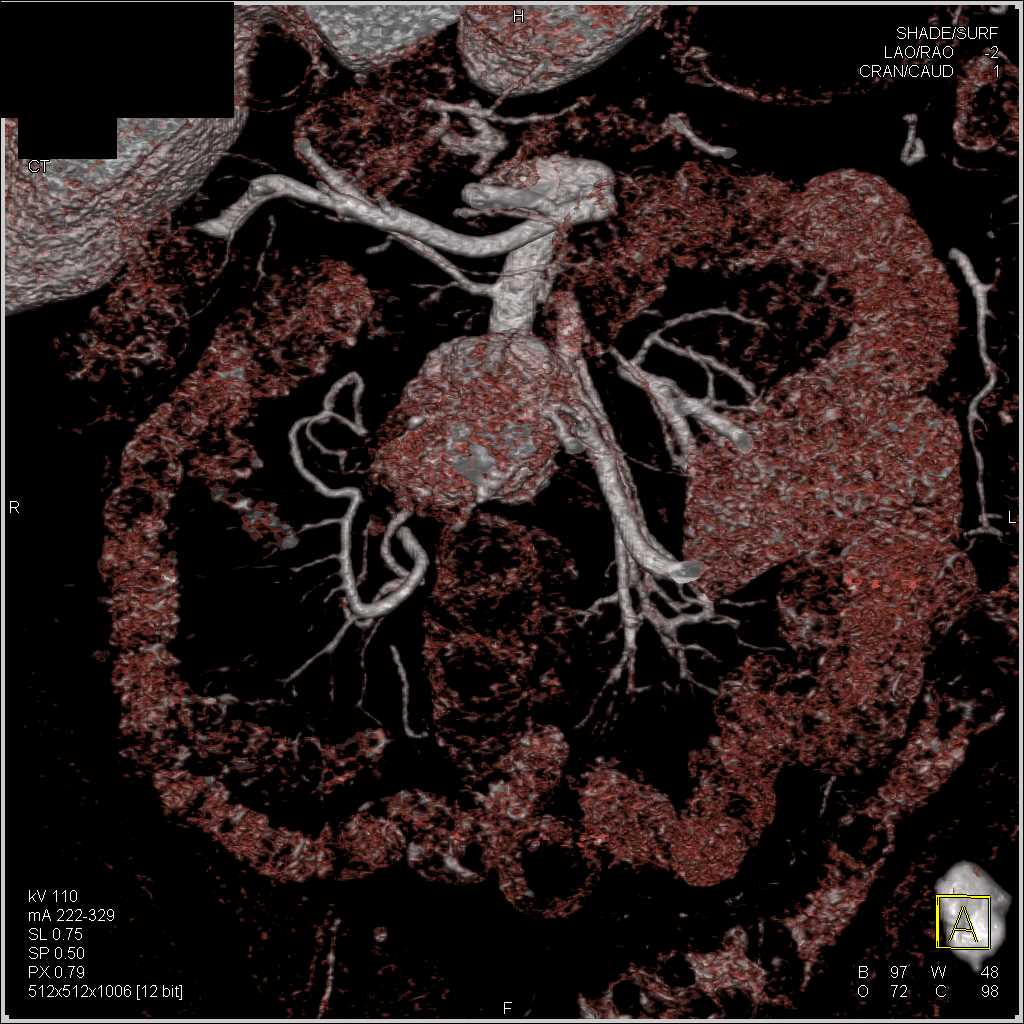

Carcinoid Tumor with Desmoplastic Reaction